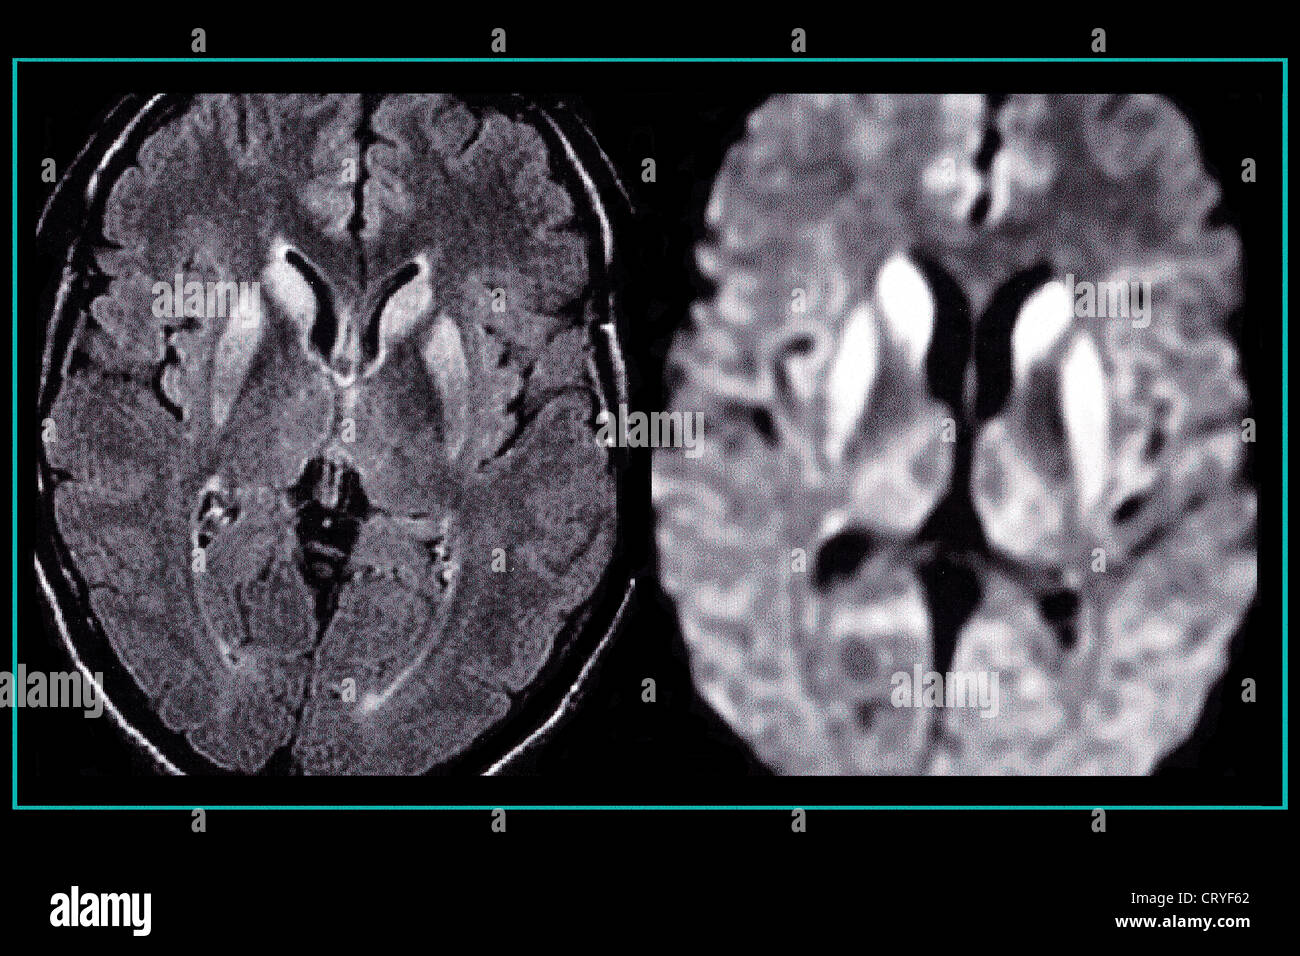

- Magnetresonanztomographie (MRT): Eine MRT des Gehirns kann charakteristische Veränderungen zeigen, die auf CJK hindeuten.